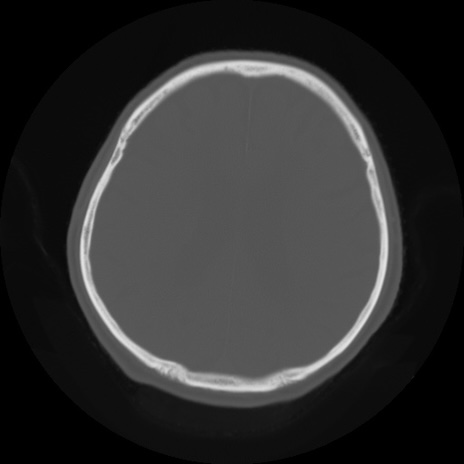

【頭部】症例5 CT(横断像)

【症例】80歳代 男性

【主訴】頭部打撲

【現病歴】外出先で椅子から立ち上がる際に、つまづいて後方へ転倒し受傷。転倒時に意識はあった。

【既往歴】高血圧、不整脈、アルツハイマー病

【身体所見】BP 217/71、HR 96、JCS1-1、 難聴あり、顔色良好、右後頭部に擦過創あり。神経学的異常なし。

症例5の画像所見と診断は?